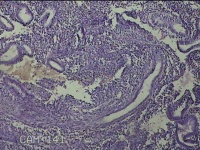

性别

女

年龄

36岁

临床诊断

子宫肌瘤 子宫异常出血 子宫内膜增生

一般病史

断续阴道流血多10天。

标本名称

子宫腔内膜

大体所见

灰白暗红色不规则碎组织3x2.8x0.8cm一堆。